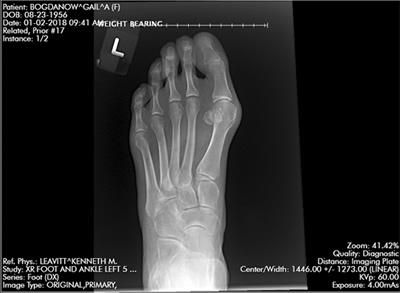

Pleased with Hammer Toe/Bunion Reconstructive Surgeries

By Gail Bogdanow

"Having seen what hammertoes did to my mother's quality of life, I knew that I would have to be proactive in my life. In addition I also had bunions on both feet. The pain and discomfort were still tolerable but I knew that they would only get worse with time. Something as simple as wearing a basic dress shoe and therefore a skirt was becoming more and more difficult. After much research on procedures and doctors, I felt very confident in choosing Dr. Leavitt.

"We bought a knee walker that proved indispensable. We also borrowed a tub transfer bench from our town's senior center for showering as well as a dry cast protector. Every home is different but there are some preparatory basics. There were seven weeks in a cast followed by learning to walk again and several weeks using the Dynasplint devices. I was so pleased with the outcome that I had the second, less deformed foot, reconstructed as well. I am just as pleased with the results and my marriage is still strong."